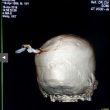

GHODEGAON – Un 19enne originario dello Stato indiano del Maharashtra è stato sottoposto ad un delicatissimo intervento chirurgico dopo che gli è finita conficcata in testa una chiave da moto, che se si fosse posizionata pochi centimetri più in là lo avrebbe ucciso.

Il giovane ha subìto il terribile infortunio durante una rissa nel villaggio di Ghodegaon nel distretto di Ahmednagar. È stato dimesso tre giorni dopo l’incidente e pare si stia riprendendo.

“Questa settimana è previsto un controllo di routine, ma le sue condizioni fanno ben sperare”. Le immagini rilanciate da Dagospia sono molto forti e mostrano chiaramente le chiavi conficcate nel cranio.